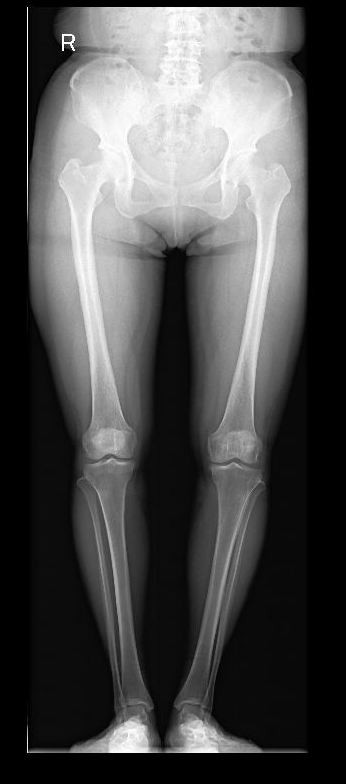

图1 膝骨关节炎x片表现:a早期

图1 膝骨关节炎x片表现:b中期

图1 膝骨关节炎x片表现:c晚期

膝骨关节炎的早期表现为膝关节疼痛,随着病情进展,会出现疼痛加重并活动受限,关节畸形。患了膝骨关节炎该如何治疗?首先需明确, 治疗的目的主要是2个,即解决疼痛,改善关节功能。 解决了这两个问题,最终就会实现生活质量的提高。那么如何缓解疼痛?怎样改善功能?这是每个膝骨关节炎患者最关心的问题,这需要根据病情的严重程度,采取个体化的治疗手段。患者希望以最小的代价获得最满意的疗效,这也是医生不竭的医术追求。